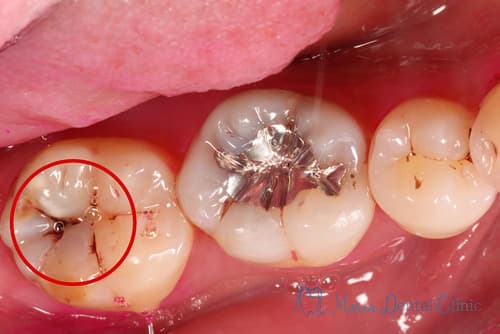

虫歯治療の写真

繰り返される虫歯治療

歯科医院で虫歯治療を行ったのに、数年後にまた虫歯になってしまい再治療が必要になってしまったという経験はありませんか?

虫歯治療中の写真

• う蝕検知液染め出し後と虫歯除去後の写真

虫歯を除去する際には、臨床感や手指感覚に頼らず、う蝕検知液を用いて虫歯を染色することが大切です。

そして、ライト付きのルーペやマイクロスコープなどの拡大下において、染色された虫歯を徹底的に除去し、且つ健全な歯質をできる限り保存することが重要です。